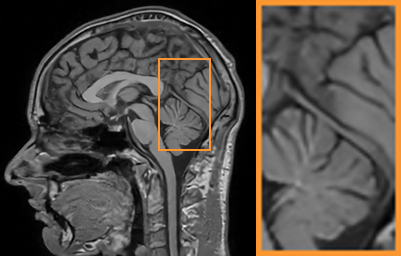

| Ground Truth (PSNR) | PANO (27.73) | FDLCP (26.84) | BM3D-MRI (26.27) | Ours (28.22) |

As shows in Fig. 1, at the first several iterations, the loss of is slightly larger than that of . Because the input is corrupted with severe artifacts, thus the role of data-driven module is significant at the first several steps. But as process goes on, repeated denoising operation in turn causes over-smoothing. While module can make up for it by incorporating model based knowledge. Though can improve the performance, it cannot ideally converge to a desired solution. The solid line indicates the superiority of Ours over other choices in both convergence rate and reconstruction accuracy. The execution time of , , and Ours is 4.4762s, 3.3240s, 6.2760s and 2.5225s, respectively. As expect, the proposed method provides a much faster reconstruction process. Thus we can verify that our framework has higher efficiency both in terms of theoretical convergence and practical execution time. The visualized results in Fig. 2 also verify that Ours has better performance than others.

First, we test on 25 T1-weighted MRI data using three different undersampling patterns with a fixed 10% sampling rate. Fig. 3 shows the quantitative results (PSNR). Our method performances best for all three cases and has stronger stability compared with the second best method on variance. As for the effect of sampling ratios variation, we use radial mask under 10%, 30% and 50% sampling rates with evaluation of RLNE and MSE. Fig. 4 shows that our method has the lowest reconstruction error for all sampling rates. For more intuitive comparison, we illustrate the reconstruction error in term of pixels in Fig. 5. We also offer the qualitative comparison in Fig. 6. Visualized results demonstrate our method has better performance in both artifacts removing and details restoration. Time consuming is also considered. We compare our method with others on the 25 T1-weighted data using Radial mask with 10% and 50% sampling rate. Notice that ADMM-Net and ours are tested on GPU for the incorporation of deep architecture. Tab. 1 shows that our method provides an efficient reconstruction process and comes to the fastest method among the state-of-the-art competitors.